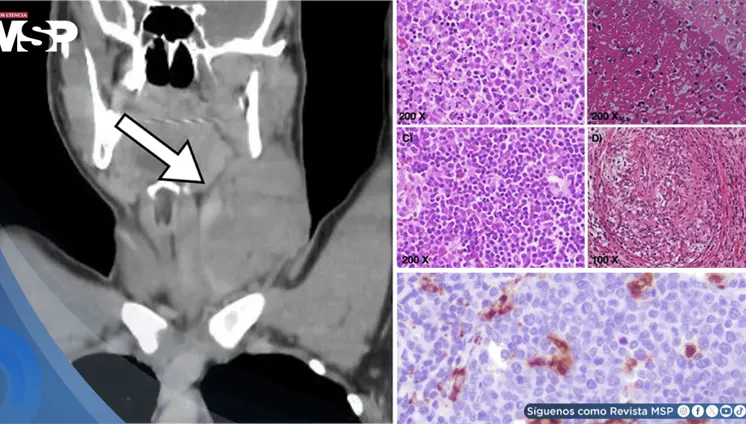

Las lesiones óseas osteolíticas, anemia y alteraciones hematológicas h...